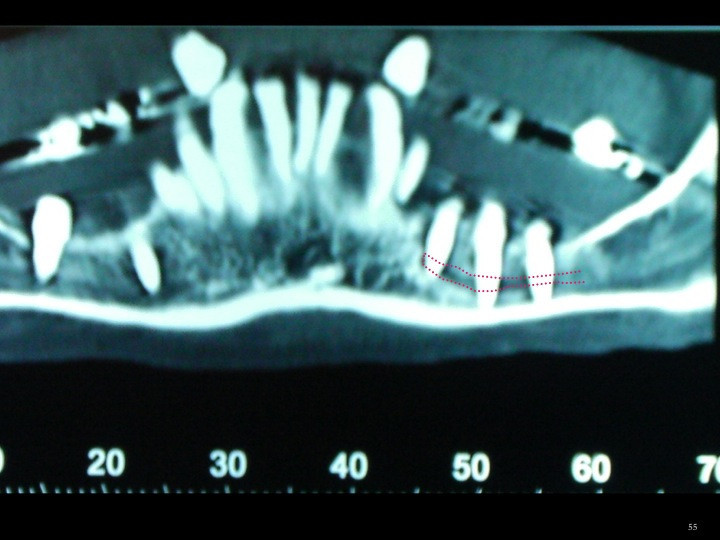

La reabsorción ósea en la mandíbula, tiene un patrón de origen vertical. Al perderse altura, la presencia de estructuras de riesgo como el nervio dentario o el búcle del mentoniano, nos limita la posibilidad de rehabilitar la zona con implantes, por el excaso caudal óseo.

FALTA DE HUESO EN ANCHURA Y ALTURA.

CASO CLÍNICO. REBSORCIÓN ÓSEA EXTREMA.LATERALIZACIÓN DEL NERVIO DENTARIO.

CASO CLÍNICO. REABSORCIÓN ÓSEA EXTREMA.                                 LATERALIZACIÓN DEL NERVIO DENTARIO.

CASO CLÍNICO.REABSORCIÓN ÓSEA EXTREMA.LATERALIZACIÓN DEL NERVIO DENTARIO.

CASO CLÍNICO.REABSORCIÓN ÓSEA EXTREMA.LATERALIZACIÓN DEL NERCIO DENTARIO.